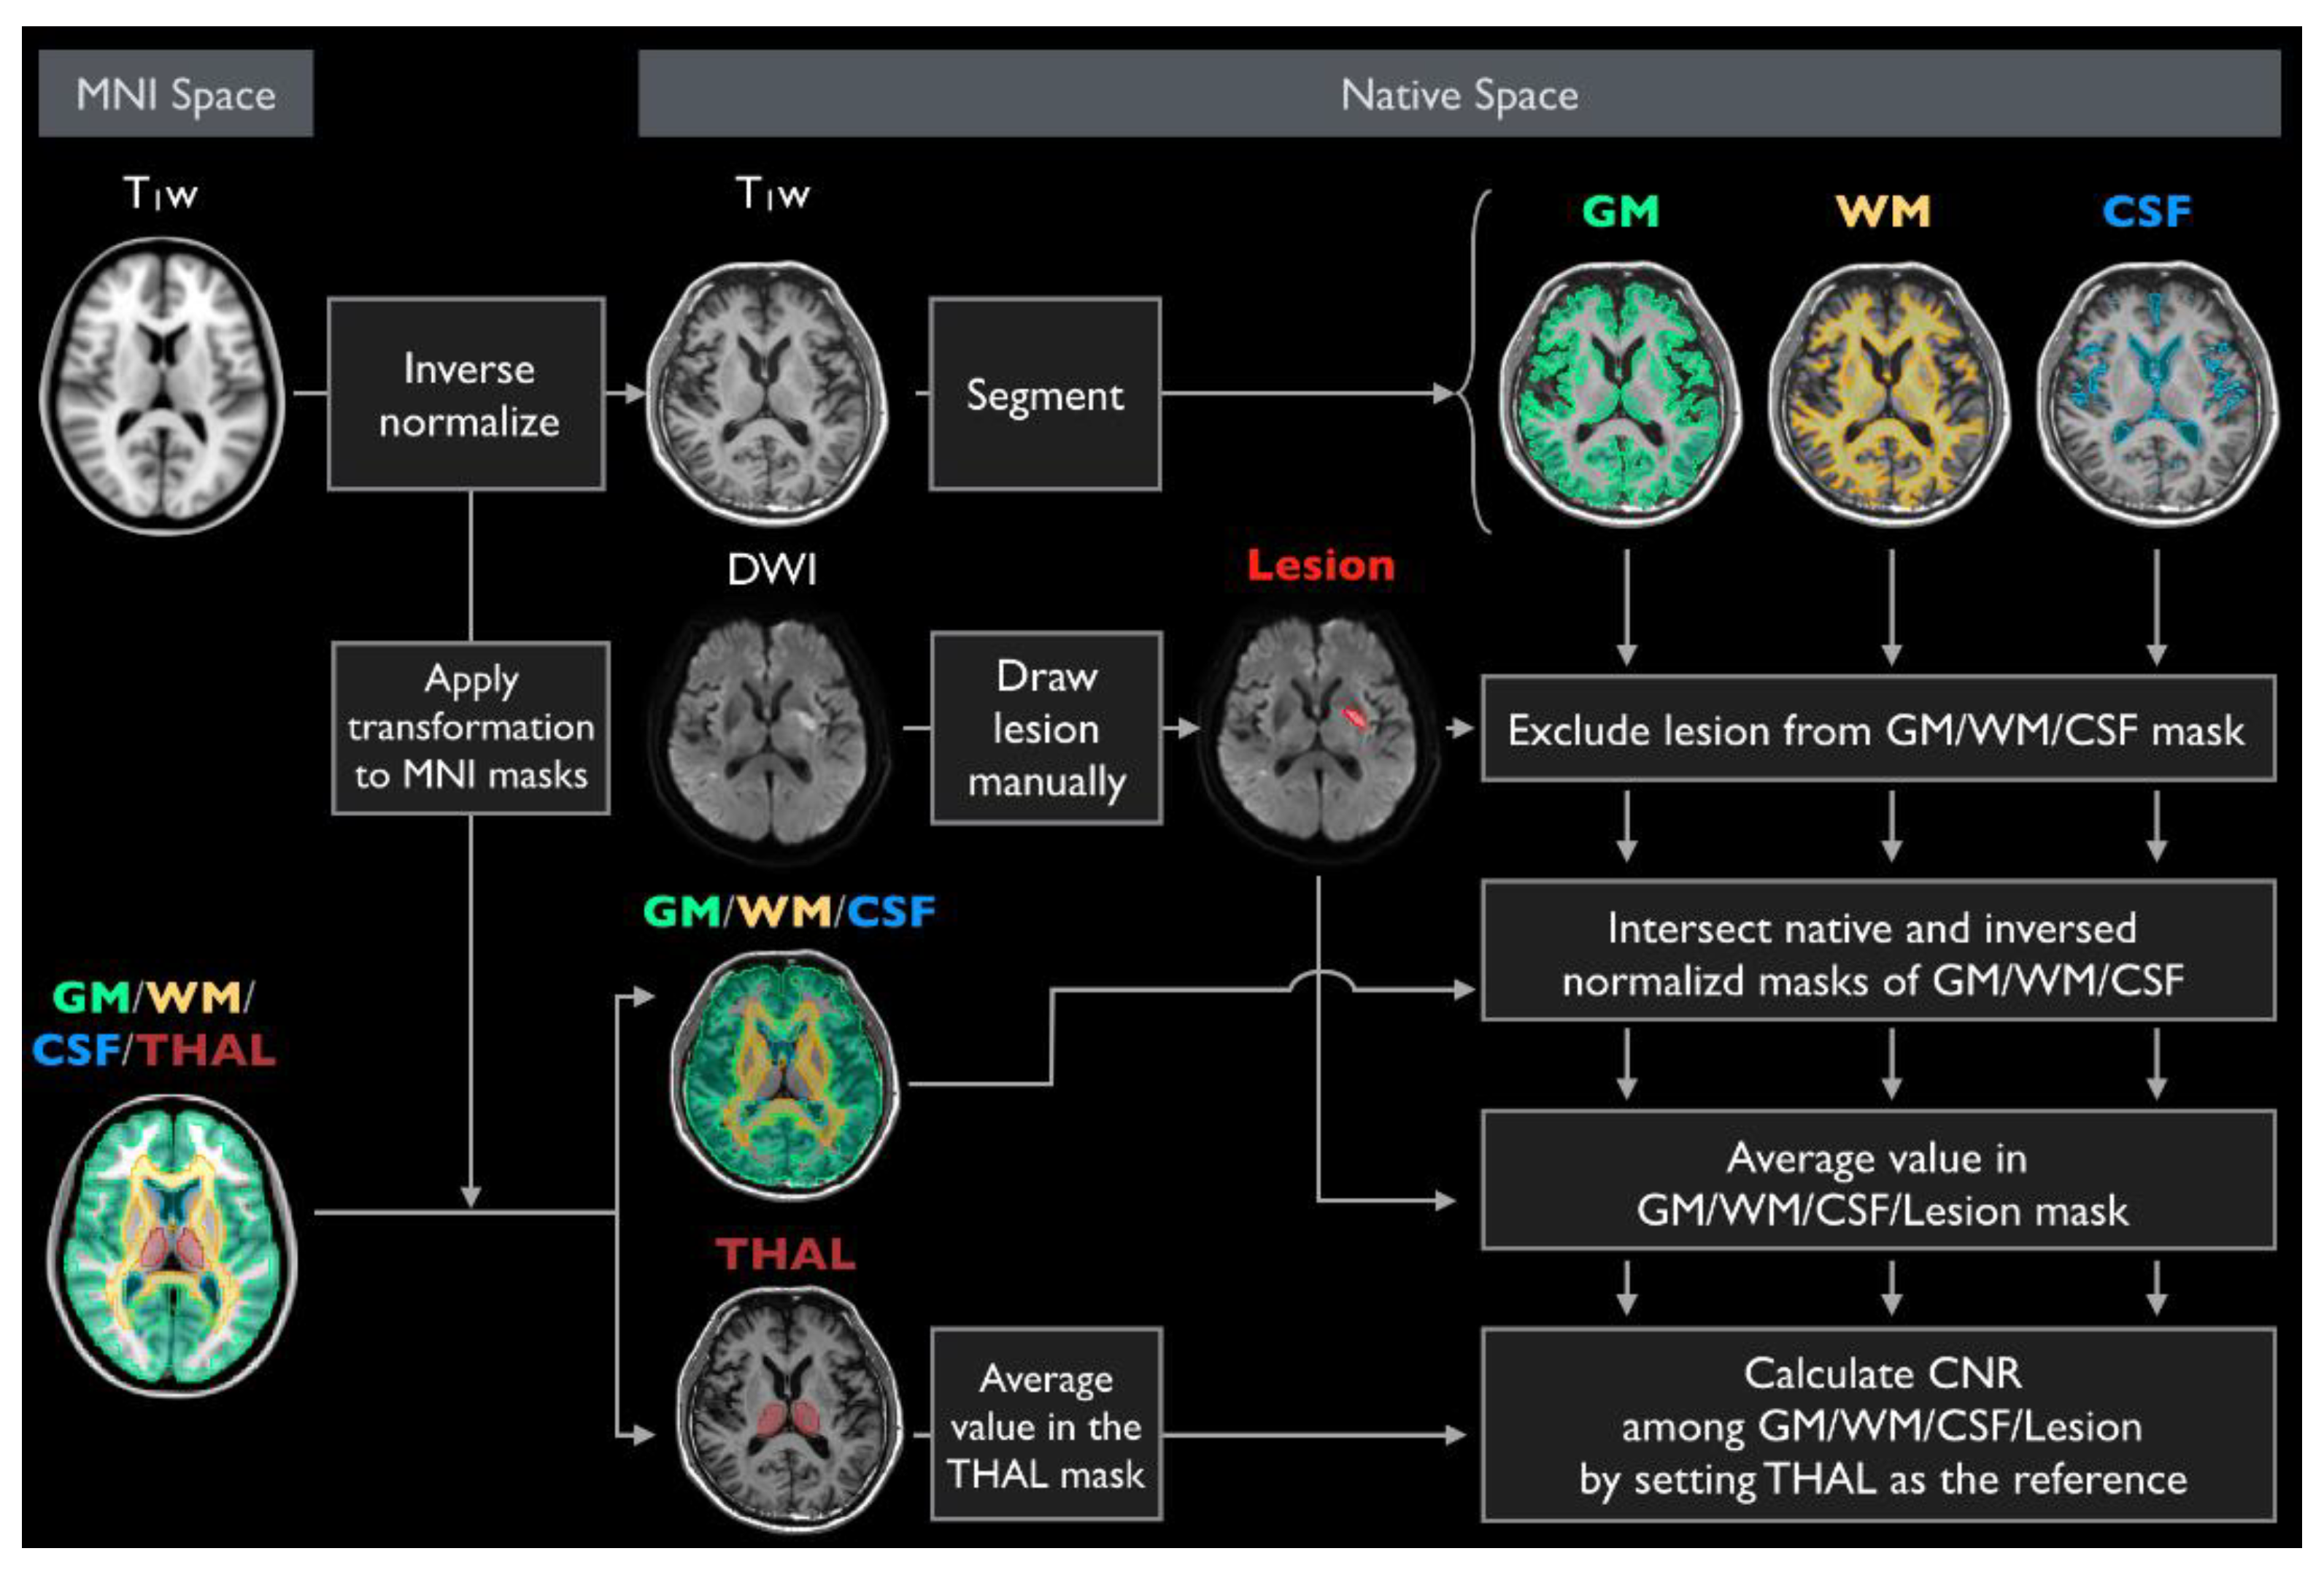

2.4. Participant and Diagnostic Score Evaluation

3.2. Participant Evaluation

4. Discussion